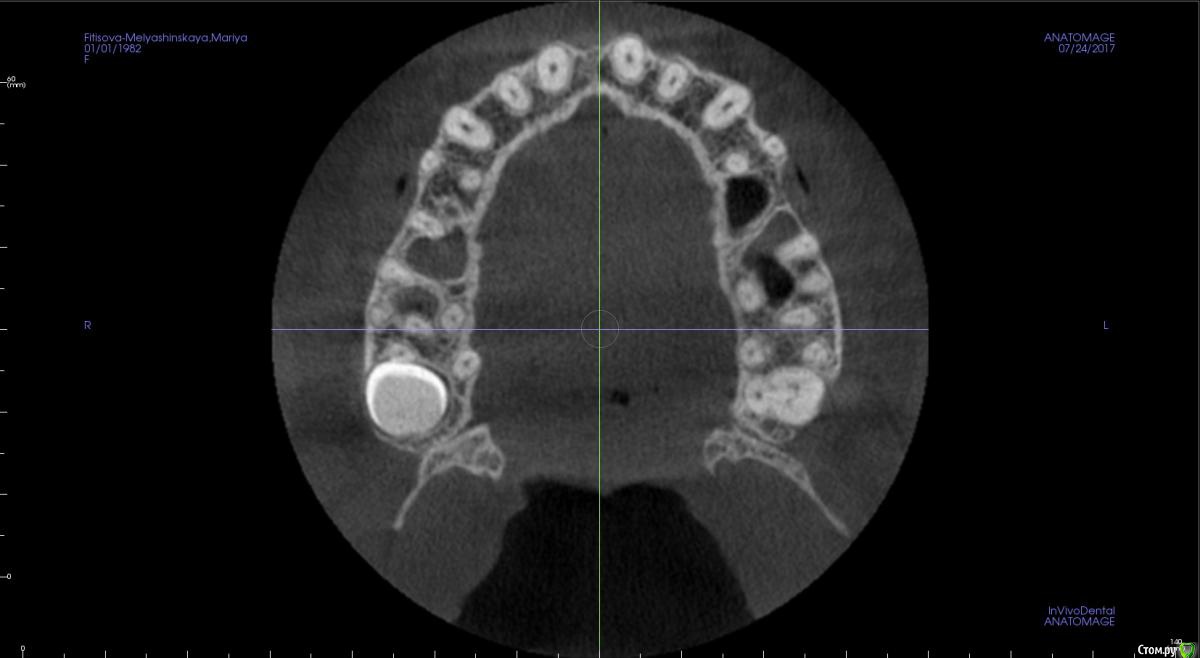

kamranchick Опубликовано 24 июля, 2017 Поделиться Опубликовано 24 июля, 2017 Ребятулечки, а можно тут как то поставить имплантат, без инвазии?В принципето молоток приветствуется если он тут сработает и сработает ли.хочу поставить 3.5 на 8.5 Ссылка на комментарий

kamranchick Опубликовано 24 июля, 2017 Автор Поделиться Опубликовано 24 июля, 2017 Сработает. Комп рисует без 1,5-2 мм, так что очень даже. Апикально кость с фрезы прям в перегонку стукнуть?))) Ссылка на комментарий